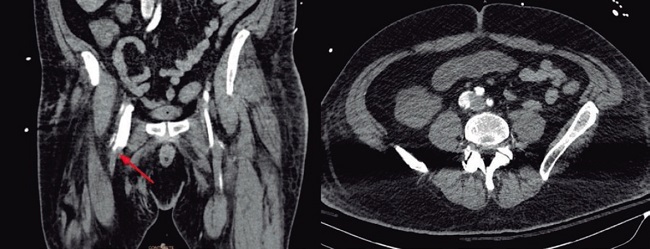

Poco después, el paciente desarrolló un cuadro de shock acompañado de hipoperfusión en la pierna derecha (según lecturas de la espectroscopía cercana al infrarrojo [NIRS] del 17% en la pierna derecha y del 59% en la izquierda). No se observaron cambios evidentes en el electrocardiograma, la ecocardiografía ni en la coronariografía. El análisis de la forma de onda de presión arterial reveló un alto gasto cardíaco, una mayor presión venosa central y un índice de resistencia vascular sistémica bajo. Una angiografía por tomografía computarizada confirmó la presencia de una fístula arteriovenosa de alto flujo entre la vena y arteria femorales derechas (figura 1; la flecha roja muestra una comunicación tubular entre los 2 vasos). Se realizó una prueba de compresión de 10 minutos (tabla 1 y figura 2) para valorar el impacto hemodinámico de la fístula en la que se observó un aumento de la presión arterial media, una disminución del gasto cardiaco y de la integral velocidad/tiempo a nivel del tracto de salida del ventrículo izquierdo, y una reducción significativa de la saturación venosa central de oxígeno.